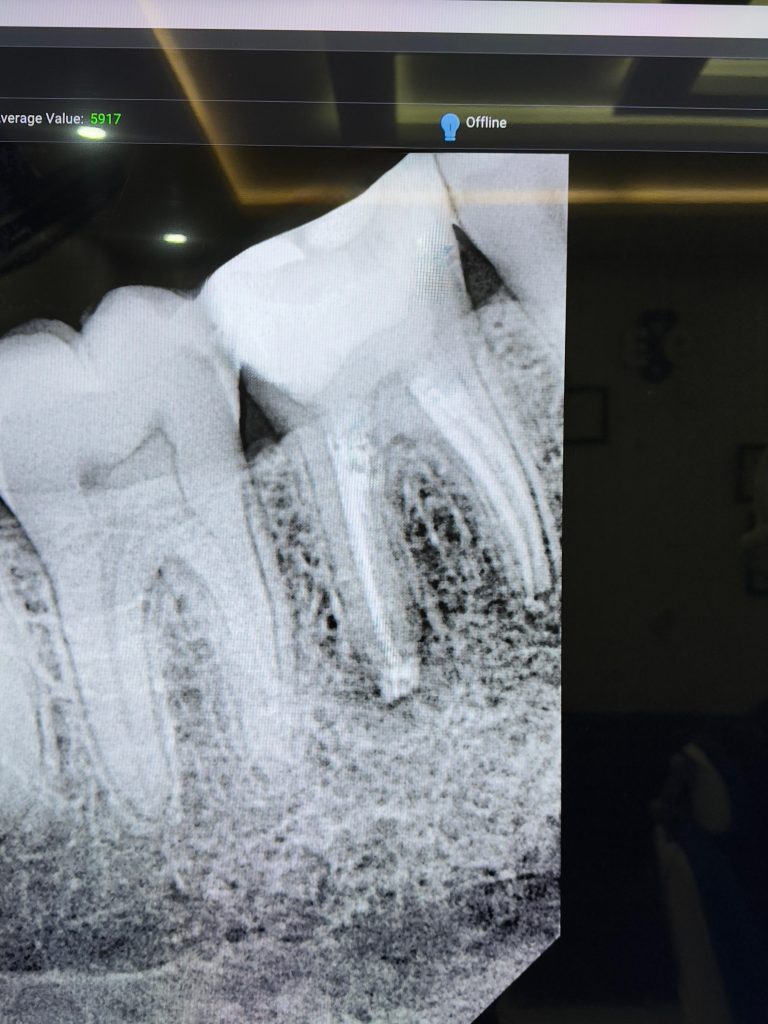

Clinical and Radiographic Findings

- Inadequate root canal obturation with voids.

- Missed canal anatomy suspected.

- Overhanging proximal restoration and subgingival distal margin.

- Associated periapical radiolucency.

- Compromised coronal seal.

- Thick secondary dentin and occlusal attrition pattern.